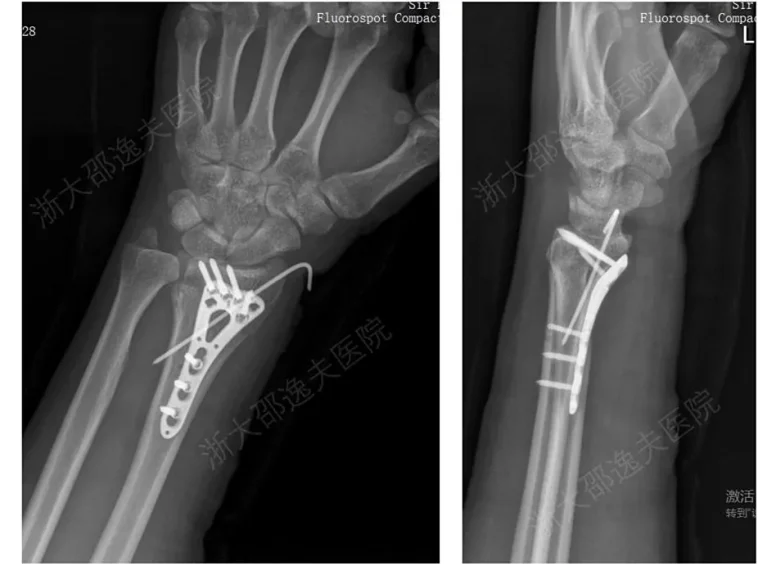

In clinical application, one young worker with a shattered wrist was treated using “Bone 02.” Surgeons made only a 2–3 cm minimally invasive incision, and within three minutes the fragments were fixed in place. Three months later, review showed excellent healing and full restoration of wrist function — avoiding the trauma of traditional open surgery and the pain of secondary operations.